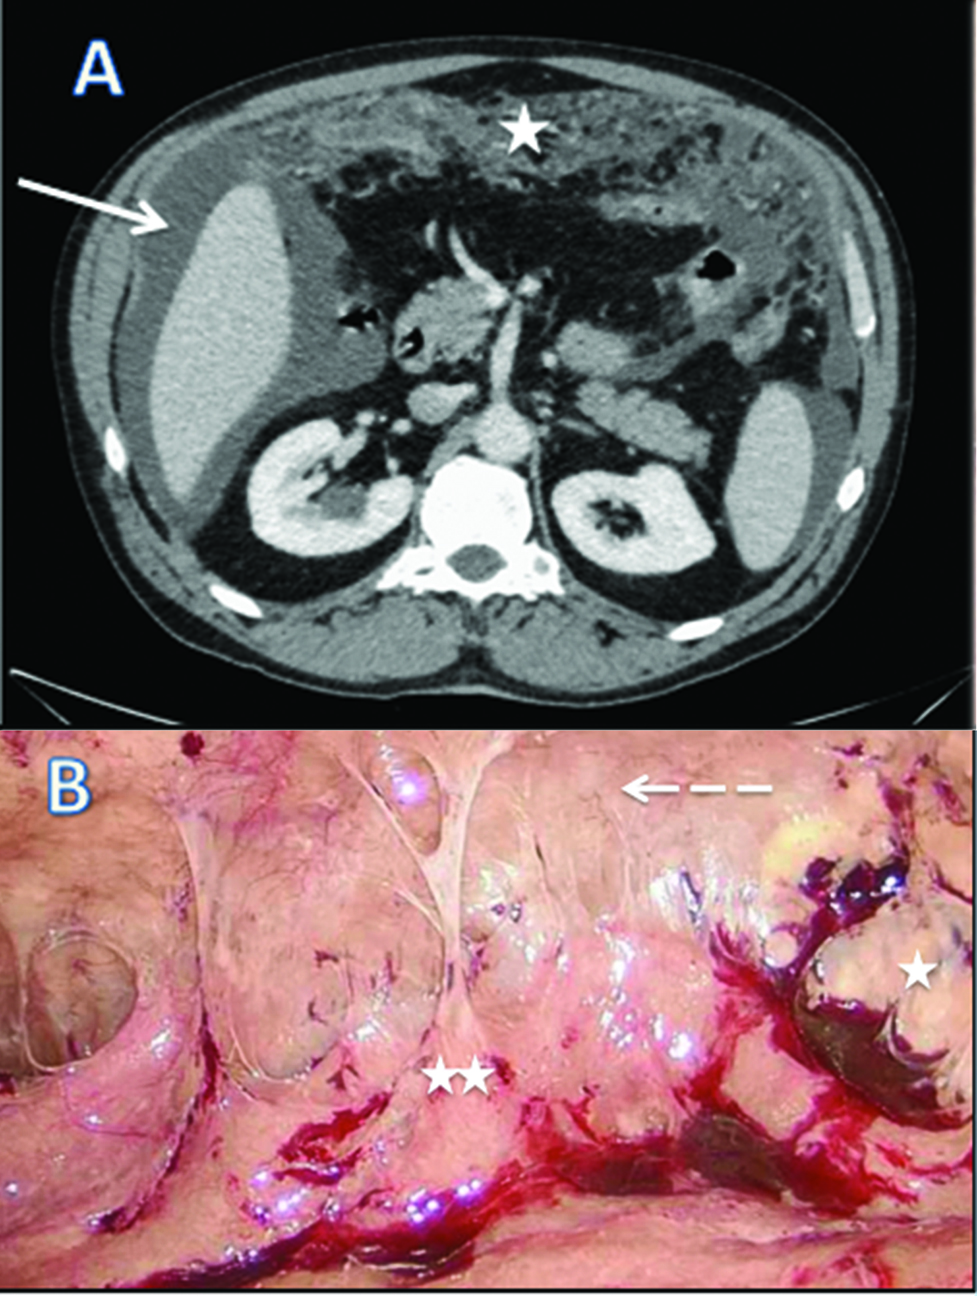

We report a case of 55-year-old male with the diagnosis of malignant peritoneal mesothelioma (MPM). Initial evaluation with CT-scan and laparoscopy reveals unresectable peritoneal carcinomatosis with PCI at 39 with thickened omentum (star), small bowel (2 stars) and parietal peritoneum (dash-arrow) deposit, ascitis (plane-arrow) (Figure 1A, B). Bidirectional chemotherapy (BDC) has been performed after three cycles of intravenous (IV) CISPLATIN – PEMETREXED, with intensification combining three cycles of IV PEMETREXED with intraperitoneal (IP) CISPLATIN (Figure 2). At reevaluation, PCI was still at 39 with a macroscopic response (Figure 3A, B). The peritoneal disease was thinner allowing a complete CRS with DOXORUBICIN/CISPLATIN based-HIPEC.

CT scan (A) and laparoscopic evaluation (B) at diagnosis of malignant peritoneal mesothelioma.